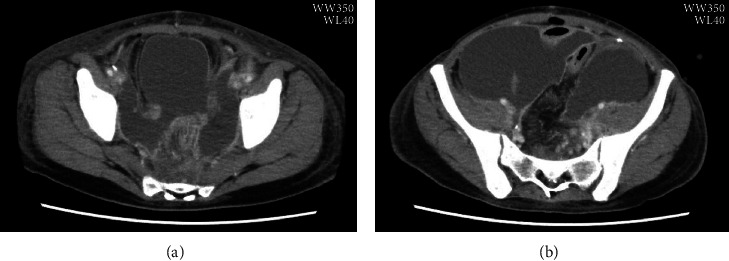

Ureaplasma parvum is one of the most common endemic mycoplasmas in the genitourinary tract and can cause amniotic fluid infection leading to preterm labor. We report a rare case of Ureaplasma parvum infection ascending from the vagina to the abdominal cavity after hysterectomy, causing vaginal cuff infection, postoperative peritonitis, and small bowel obstruction. A 29-year-old nulliparous woman presented with infected uterine cervical cancer. After radical hysterectomy for uterine cervical cancer, the patient had paralytic ileus with ascites and fever. Peritonitis was suspected; however, all cultures were negative, making it difficult to identify the causative organism. Polymerase chain reaction (PCR) of the ascites revealed Ureaplasma parvum, which could be treated with levofloxacin (LVFX). Open drainage to control the infection revealed a necrotic tissue around vaginal cuff and the small intestine encased in cocoon-like fibers like sclerosing encapsulating peritonitis. After the infection was improved, the bowel obstruction was also improved. Ureaplasma spp. can be difficult to culture. PCR testing for Ureaplasma infection should be considered when urogenital infection is suspected in patients prone to opportunistic infections, such as those with malignant tumors.